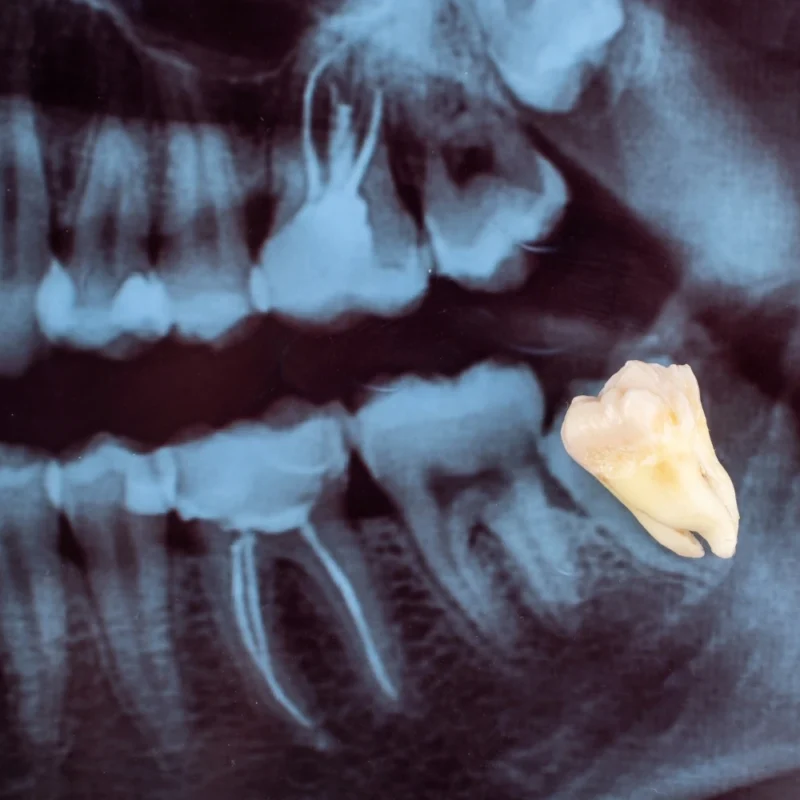

20’lik dişler, yani üçüncü azı dişleri, genellikle 17-25 yaşları arasında çıkmaya başlar. Ancak her zaman düzgün çıkmazlar. Çene yapısına uyumsuz, gömülü veya eğri çıkan 20’lik dişler ciddi ağız sağlığı sorunlarına yol açabilir. Bu nedenle birçok kişi için 20’lik diş çekimi kaçınılmaz bir ihtiyaç haline gelir.

20’lik dişler, ağızın en arka kısmında yer alan üçüncü azı dişleridir. Çoğu zaman çene kemiği yeterince büyük olmadığı için bu dişler gömülü kalabilir, yana doğru çıkabilir veya yarı çıkmış halde kalıp iltihaplanmalara neden olabilir.

Ayrıca, diş henüz problem yaratmadan önce, röntgen ile yapılan kontrollerde gömülü olduğu tespit edilirse de çekim önerilebilir.

- Muayene ve Röntgen

Dişin konumu, kök yapısı ve etrafındaki dokular değerlendirilir. - Anestezi Uygulaması